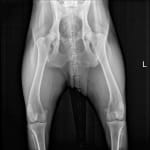

- Mildly decreased range of motion of the hips with crepitus

- No cruciate ligament abnormalities

- Radiographs

- Radiographs are normal